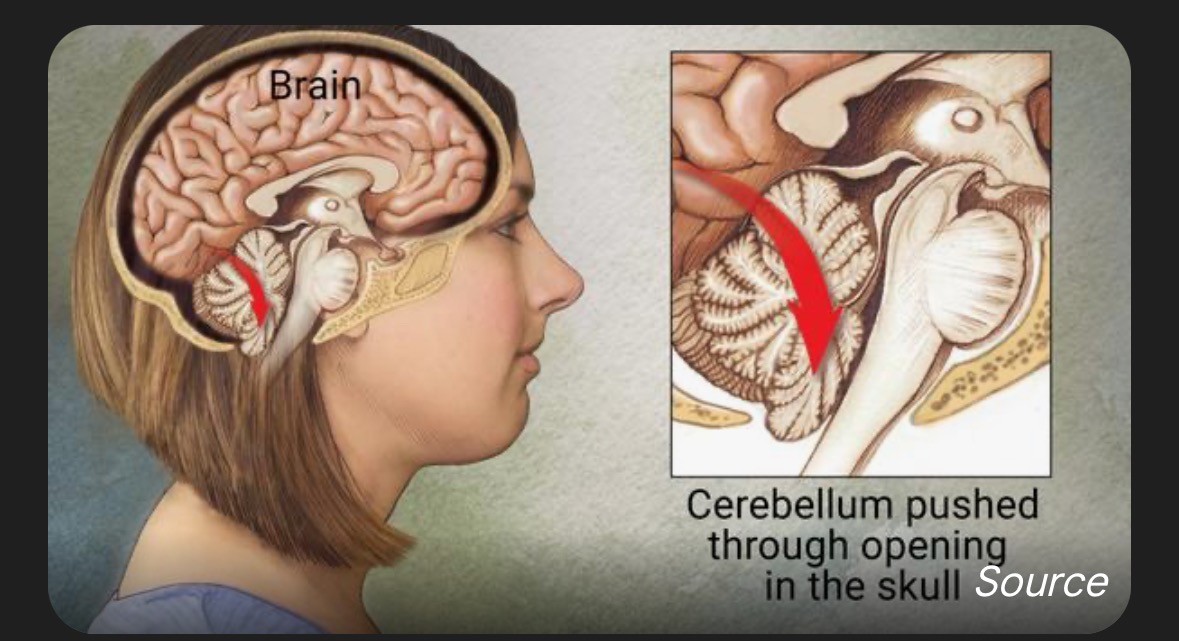

My name is Melissa, and I am facing a life-changing challenge due to Chiari malformation—a condition where brain tissue extends into the spinal canal because of a misshapen or smaller skull. This causes my brain to be pressed downward, leading to severe and frequent migraines. I experience around 22 migraines each month, many of which are so intense that I am unable to function. This has made it incredibly difficult to be present for my family and to keep up with my job. The pain and exhaustion are constant, and it has taken a toll on every aspect of my life.